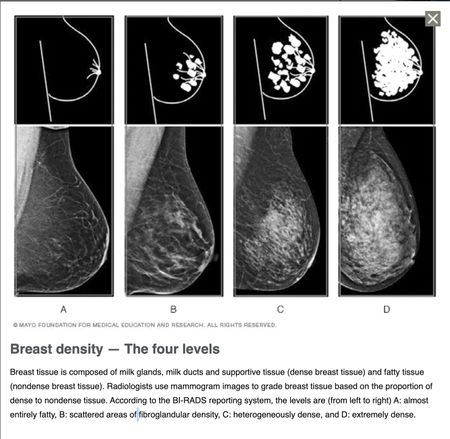

Check out these previous threads about the necessity of being advised of Breast Density - the wheels turn slowly :( (Take a note of the dates of each post ...... IT HAS TAKEN A WHILE!) - in the meantime, many women have been diagnosed with a worse stage BC than they needed ๐ก :